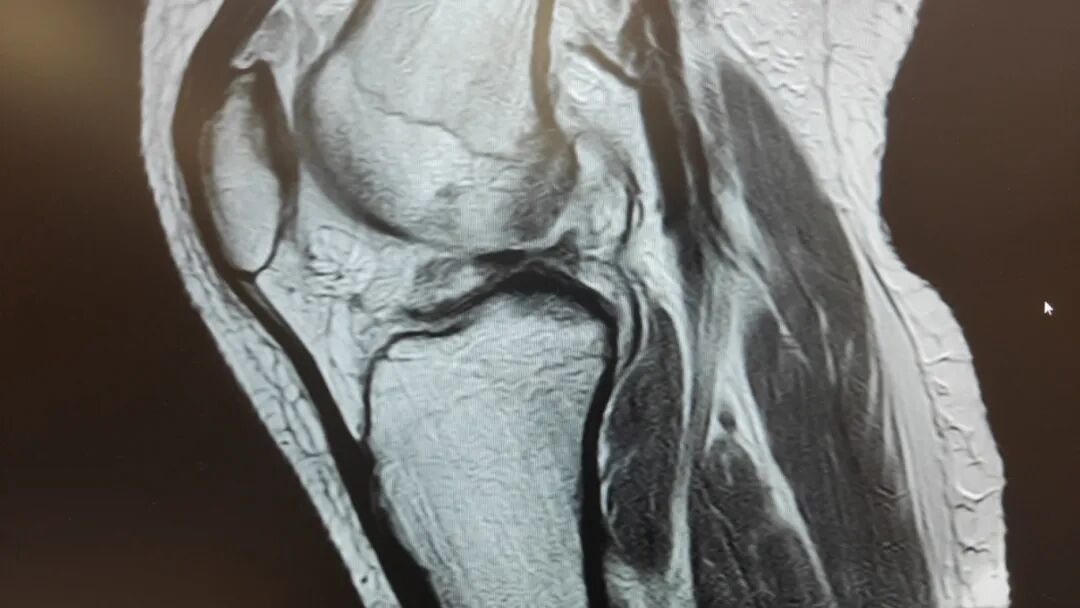

鲁先生的孩子喜欢打篮球,但在前段时间突然右膝盖疼痛难忍,甚至需要拄拐行走,严重影响日常行走,遂来我院就诊。经骨科核磁扫描发现,患者右股骨及胫腓骨远端骨质水肿,右膝外侧半月板后角、内侧半月板前后角损伤,右膝前交叉韧带、右后交叉韧带及内外侧副韧带损伤,伴有膝盖积液。

图片图片